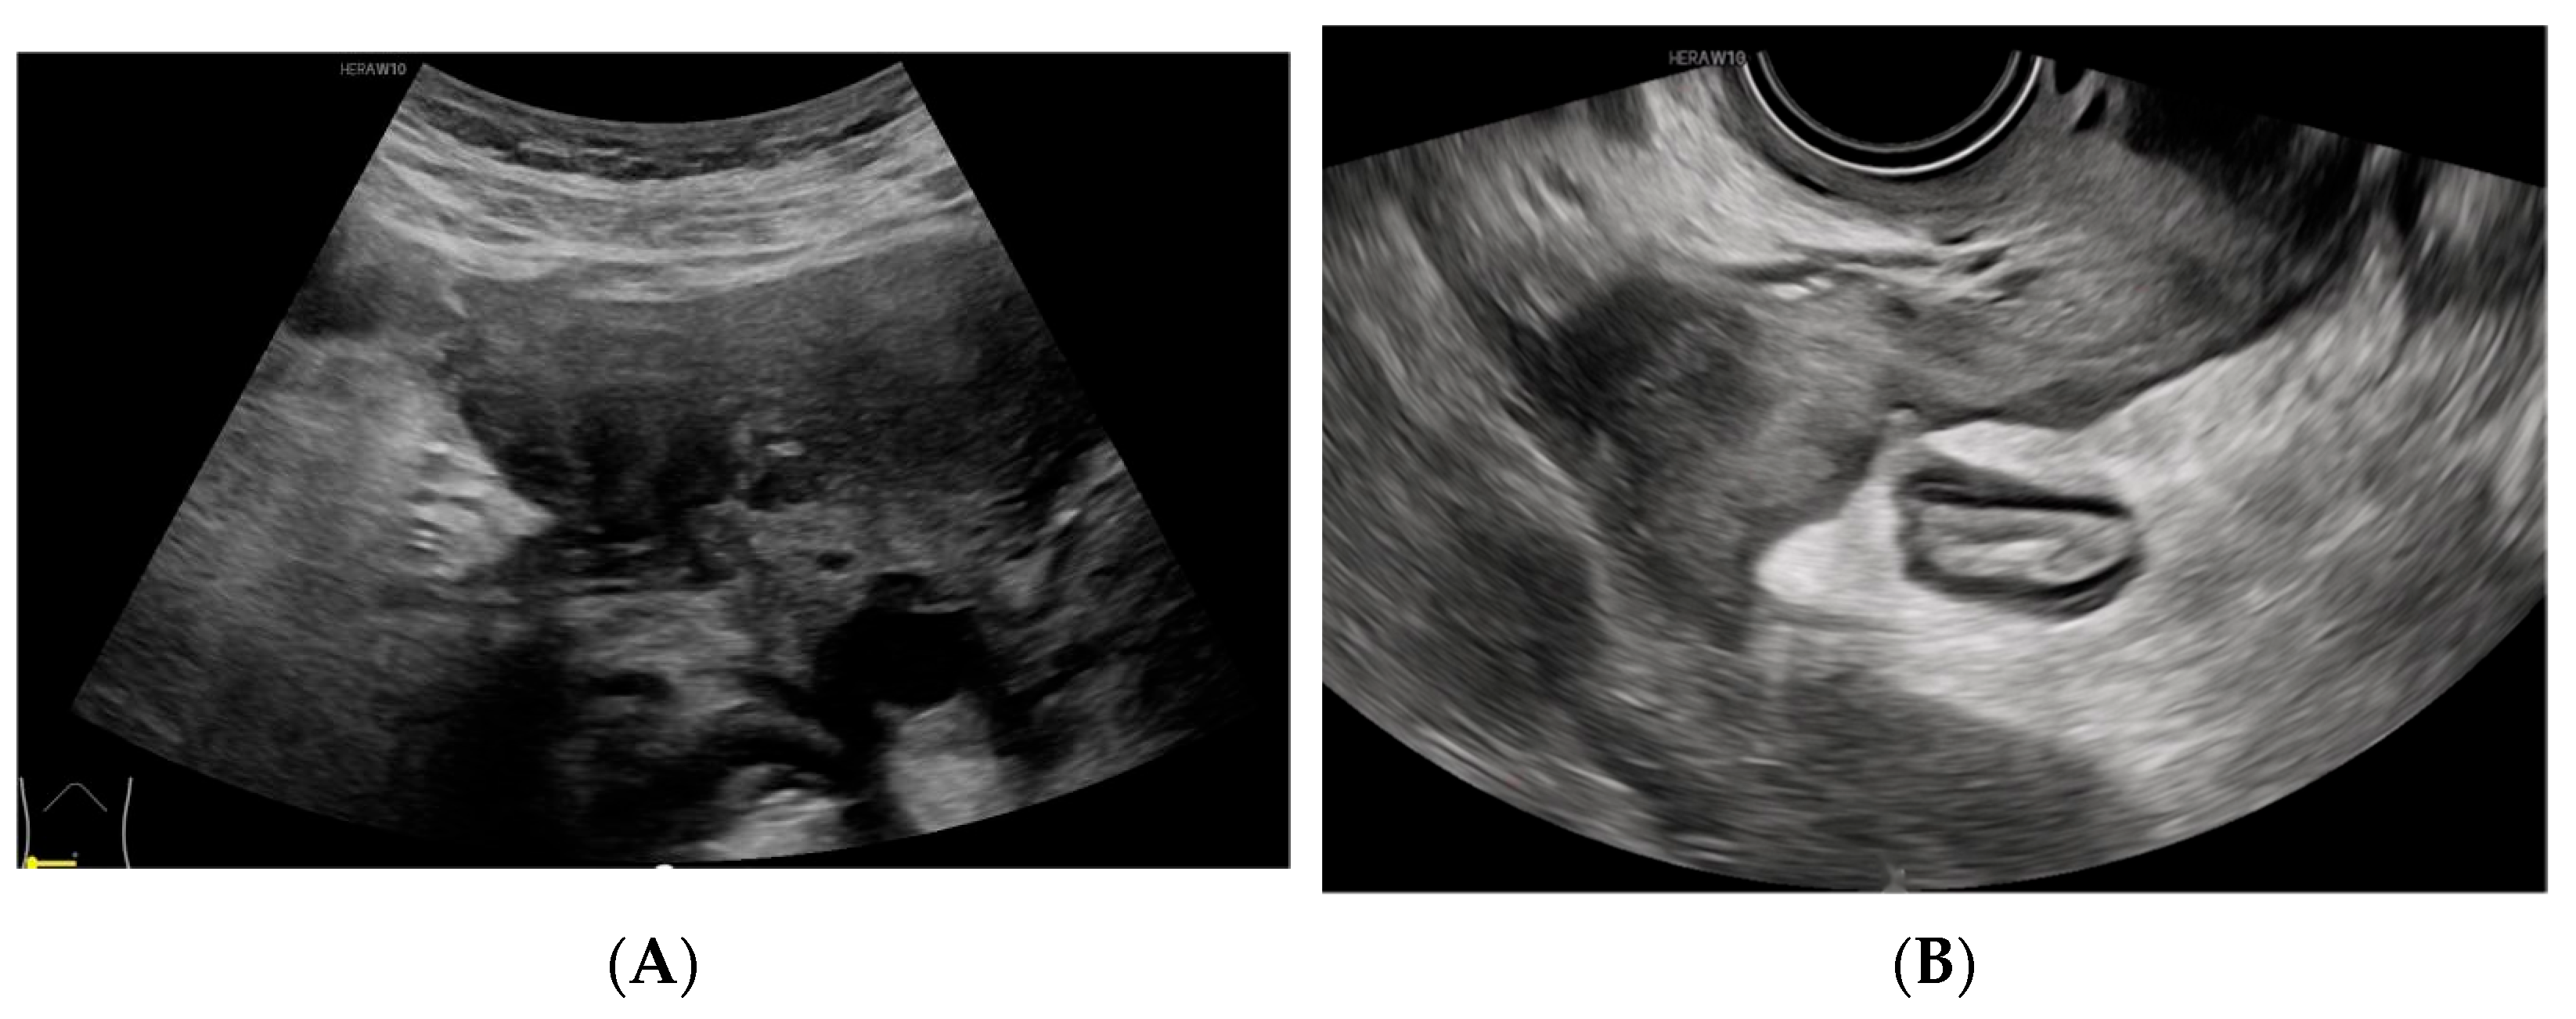

Figure 4.

(

A) A gradual reduction in the mass. (

B) The eventual resolution of the mass, confirming a diagnosis of Actinomyces infection. Pelvic actinomycosis, a rare subacute to chronic granulomatous disease, constitutes approximately 3% of all actinomycosis cases [

Figure 4.

(

A) A gradual reduction in the mass. (

B) The eventual resolution of the mass, confirming a diagnosis of Actinomyces infection. Pelvic actinomycosis, a rare subacute to chronic granulomatous disease, constitutes approximately 3% of all actinomycosis cases [